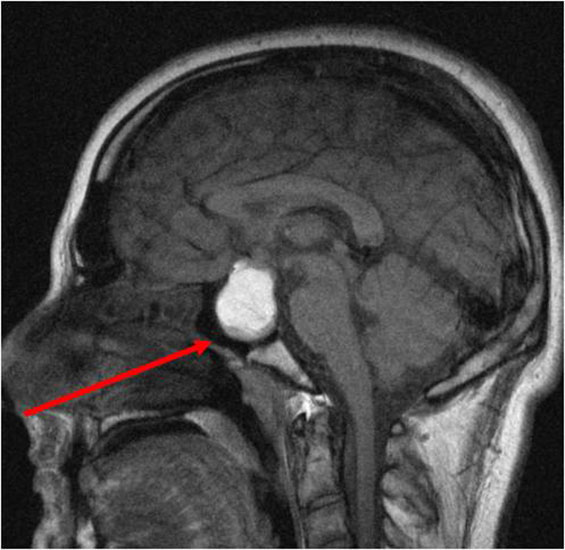

- МРТ – магнитно-резонансная томография с контрастом для улучшения визуализации опухоли. После введения контраста контуры опухоли становятся четче на фоне гипофизарной ткани. Исследование позволяет оценить размер пролактиномы и ее распространение.

- Анализ крови на пролактин. Уровень этого гормона коррелирует с размером пролактиномы. Значение выше 200 нг/л может указывать на опухоль. При незначительном превышении нормы рекомендуется повторный анализ 2-3 раза с интервалом 7-10 дней.